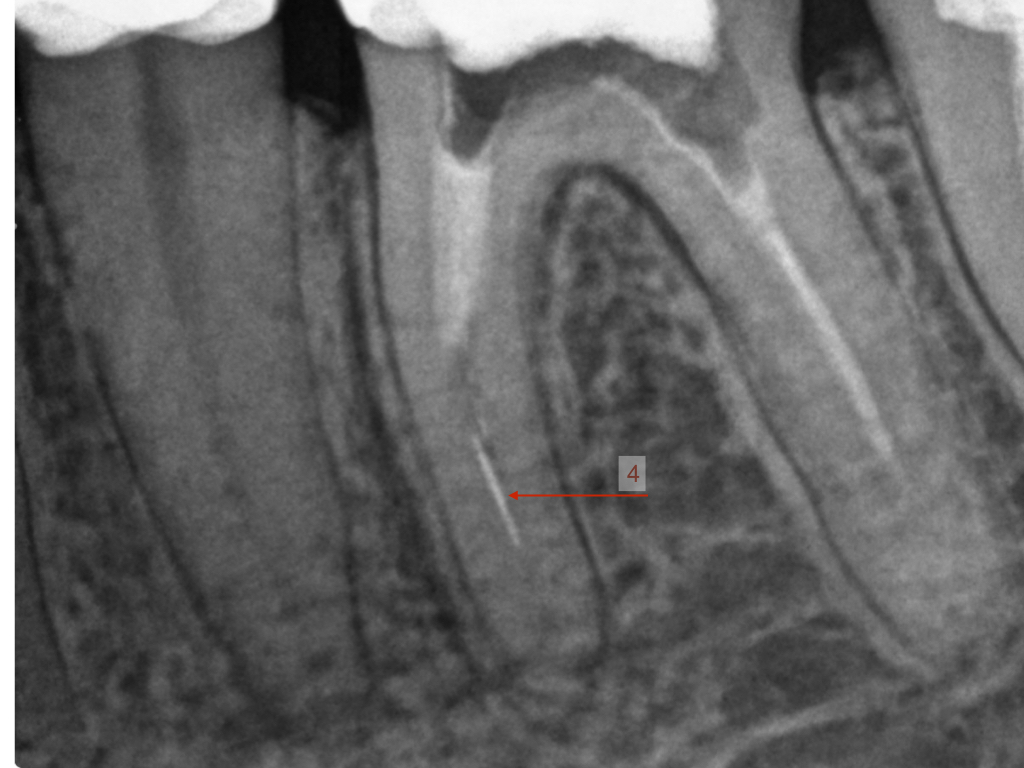

ws15102016-007

4 auf einen Streich